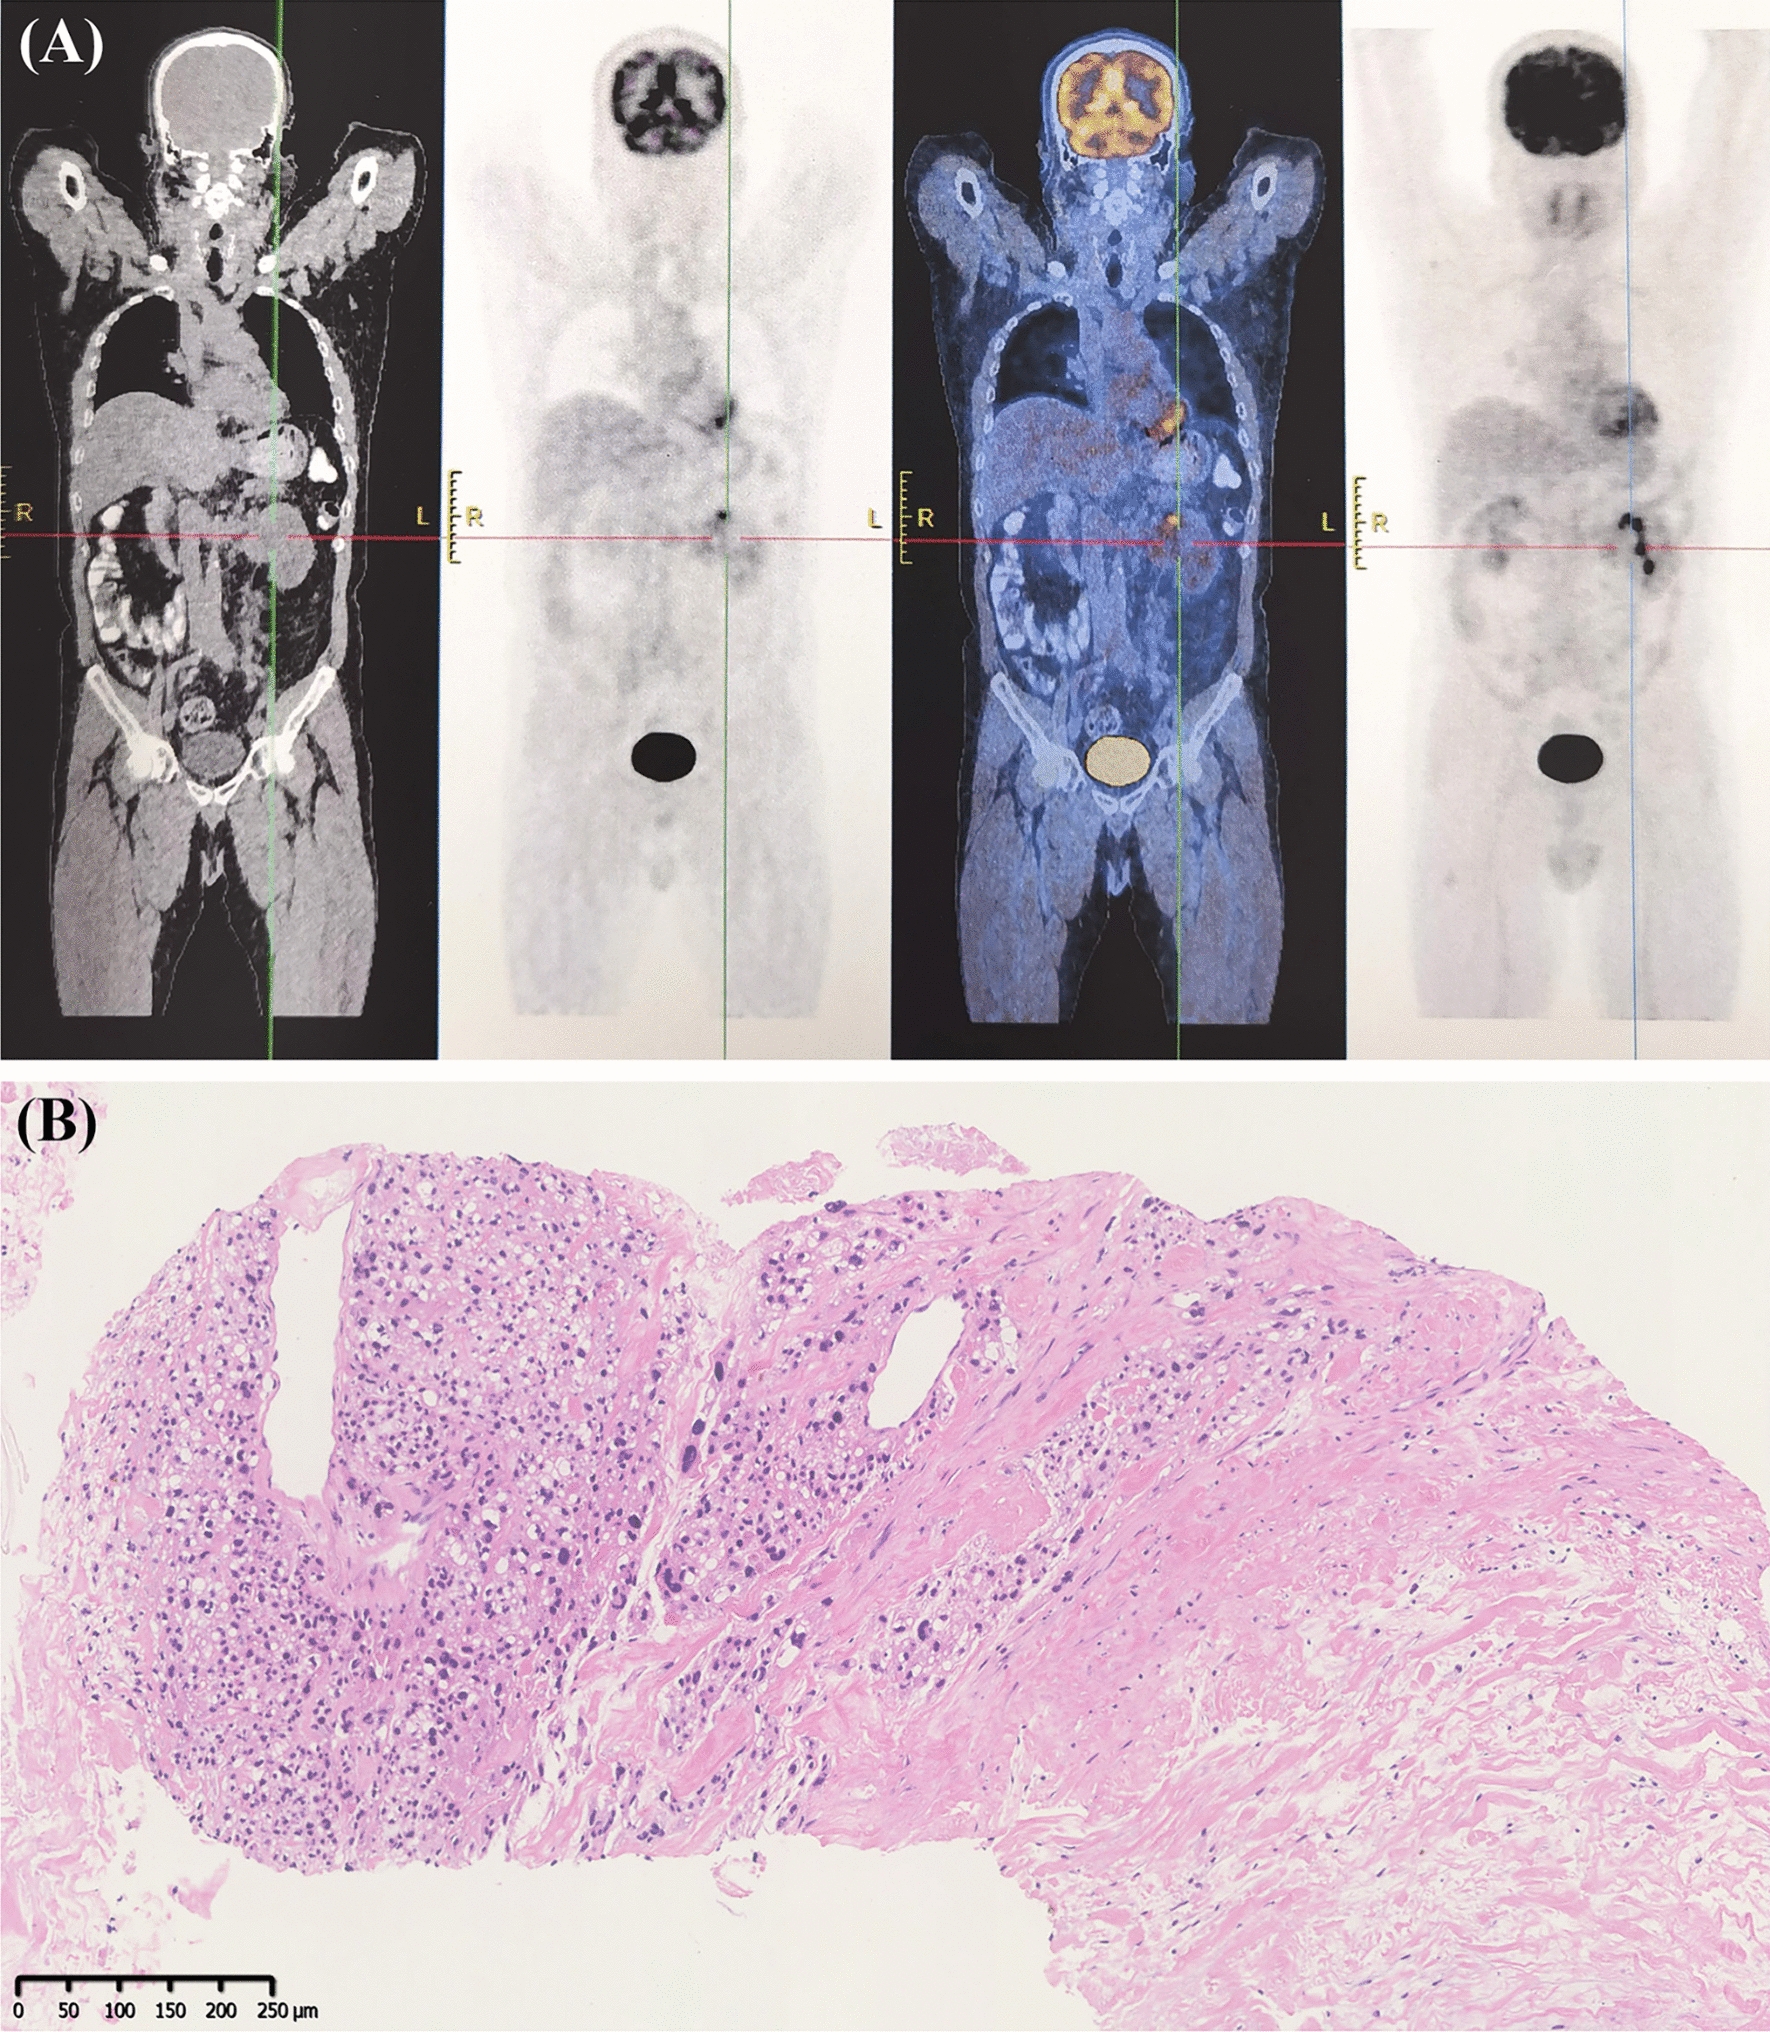

A 66-year-old man presented with a 6-month history of abdominal discomfort. Colonoscopy revealed multiple polypoid elevations (Yamada type I–III), ranging from 0.6 to 3.5 cm in size, located at various distances from the anal verge. Biopsy pathology and immunohistochemistry results suggested leiomyosarcoma (LMS). A subsequent PET-CT scan revealed the presence of left renal carcinoma (Fig. 1).

Fig. 1

PET-CT presence and pathology of renal carcinoma. A PET-CT showed a left renal carcinoma measured 7.1 cm × 5.6 cm × 5.9 cm with abnormal radionuclide concentration. B Ultrasound-guided biopsy showed heterogeneous cellular infiltration in the fibrous tissue, with partially hyaline cytoplasm, large deeply stained nuclei, and patchy necrosis, suggesting uroepithelial carcinoma or high-grade renal clear cell carcinoma